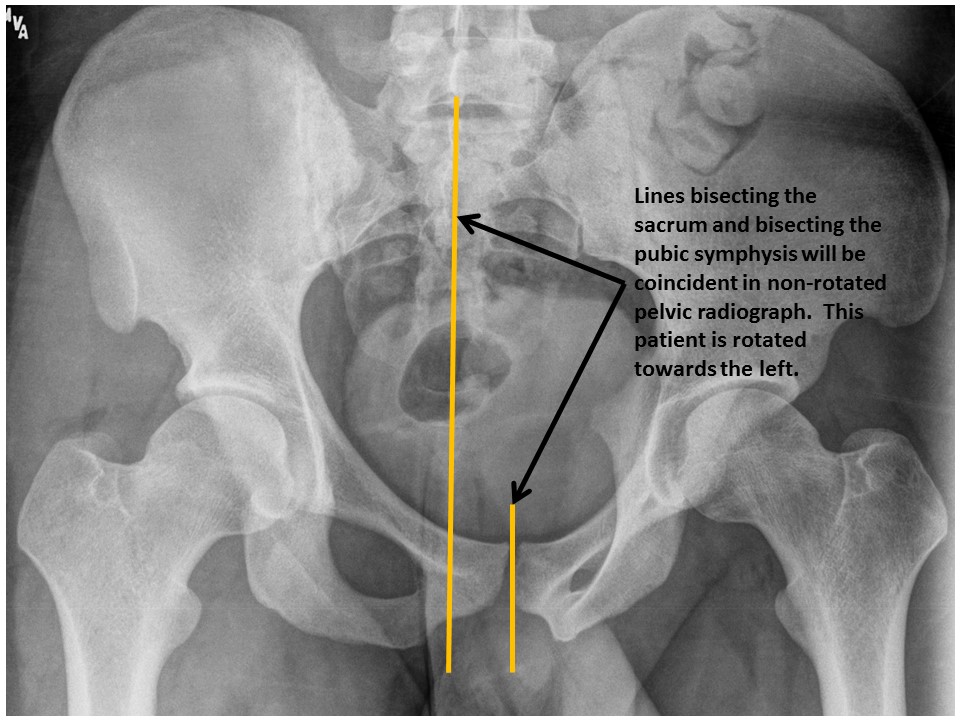

IMAGE QUALITY

The image is rotated. [Yes/No]